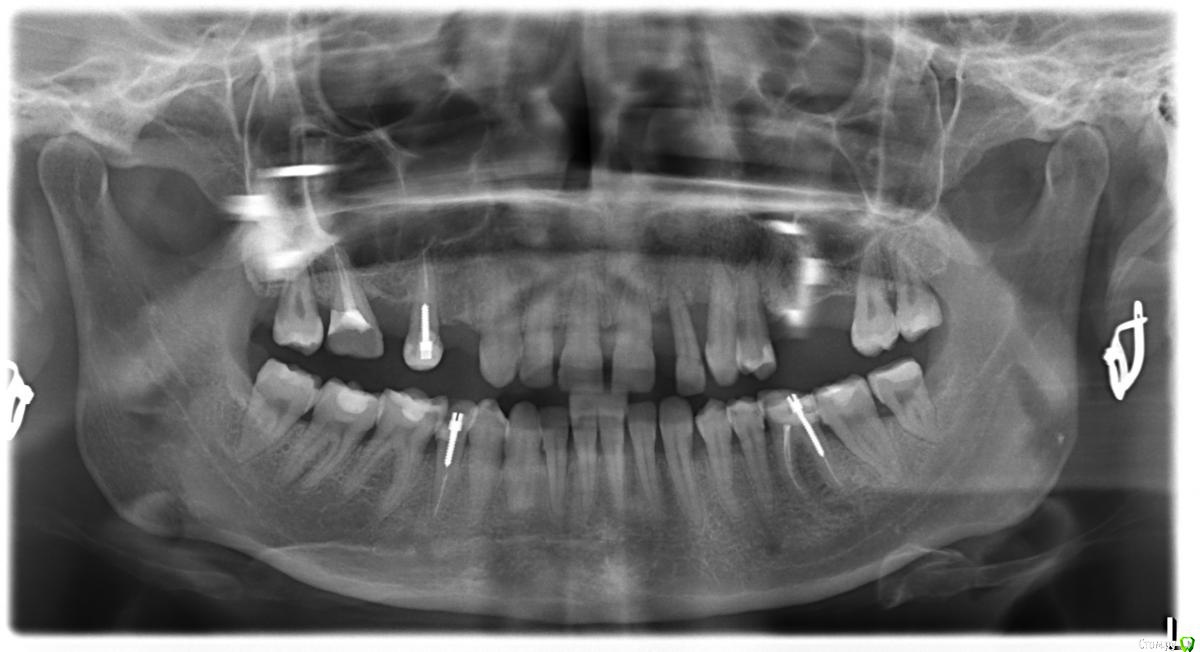

Dorin Опубликовано 12 апреля, 2016 Поделиться Опубликовано 12 апреля, 2016 (изменено) Добрый вечер! В "хирургии" уже была, три зуба слева уже удалили, теперь возник вопрос к специалистам этого раздела:Для спасения зубов в связи с атрофией кости предлагается ставить мост (ну или не знаю как правильно назвать - конструкция из коронок на предварительно депульпированные зубы + искусственные зубы) от зуба 2.1 до 1.7. На ваш взгляд, такой план лечения подходящий или есть более правильные варианты?Заранее благодарю за ответ! Изменено 12 апреля, 2016 пользователем Dorin Ссылка на комментарий

Dorin Опубликовано 13 апреля, 2016 Автор Поделиться Опубликовано 13 апреля, 2016 Какие зубы удалили? ОПТГ есть после удаления? Давайте снимок после удаления. Будем смотреть.Нет, после удаления нет снимка, удалили 2.2;2.3;2.4ОПТГ, которую в начальном посте выложила, от 26.03 Ссылка на комментарий

St. Опубликовано 13 апреля, 2016 Поделиться Опубликовано 13 апреля, 2016 Мост 1.7-1.5, Имплант и коронка на 1.4Фронт - парадонтология. Слева 2.2-2.6 импланты.Коронки внизу 3.6 и 4.5.Более опытные коллеги думаю меня поправят, если что-то упустила.. Верхние резцы Вы, увы, действительно через какое-то время потеряете. А любые большие конструкции где объединено много зубов никак не уменьшают эту вероятность, ещё и могут перегружать соседей и ухудшать гигиену. Ссылка на комментарий